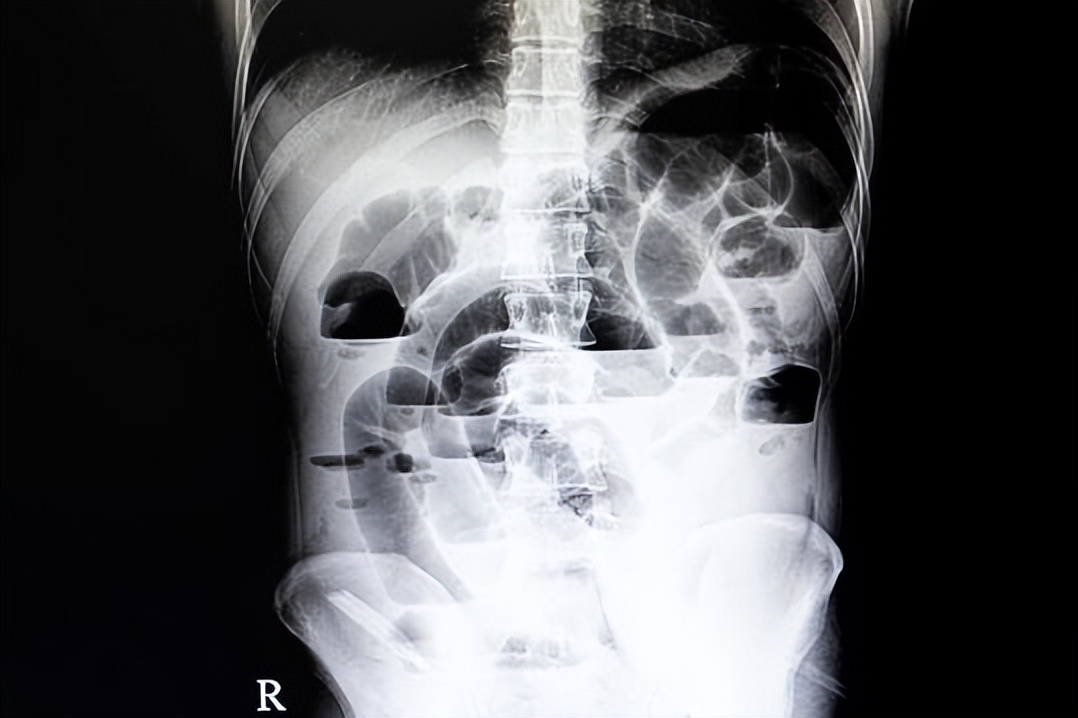

2天前小朋友哭着说疼得厉害了,吃不下东西,而且家长发现患儿排便是黑色的,次数不多,无胸闷、头晕等。随即我让患儿躺下做了查体,按压患儿腹部,有压痛,无反跳痛、肌紧张等,听诊肠鸣音正常;随后完善了相关检查,胃镜提示:十二指肠球部溃疡伴出血;慢性浅表性胃炎。故以“十二指肠球部溃疡伴出血”收入住院治疗。

结合患儿胃镜结果,以及腹痛伴黑便的表现,没有肩背疼痛,和饮食也无明显关系,所以诊断:1.十二指肠球部溃疡伴出血,2.胃炎;故入院后首先予以内科一级护理,暂禁食,然后完善了血常规、尿常规、粪便常规、胰腺炎两项、肝肾功、电解质、心电图、腹部B超和C13呼气试验查幽门螺旋杆菌等相关检查。

十二指肠球部溃疡出血是指十二指肠球部溃疡的溃疡面侵犯至深部,突破黏膜层到达肌层,侵犯血管并导致血管破裂,形成消化道出血。该类现象多见于十二指肠球部后壁的溃疡,十二指肠球部后壁位于腹膜后位,该处溃疡面侵导致十二指肠穿孔少见,多见引起血管破裂,造成出血。治疗严重出血需先在胃镜下或介入下治疗,辅助抑酸药物,如上述治疗失败,需行手术治疗,术式为出血部位的缝扎加胃大部切除。